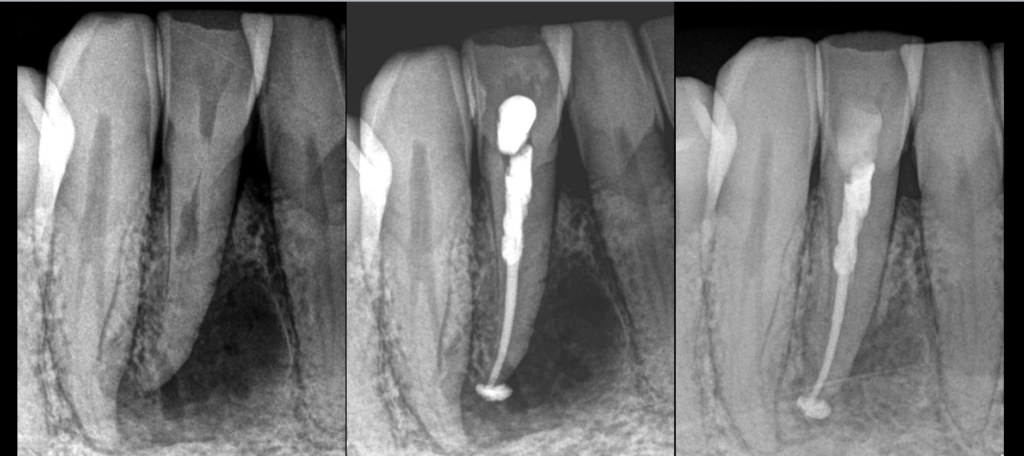

🦷 Résorption radiculaire interne de cette dent n°42.

💧 Irrigation NaOCl/HEDP activée au XP Finisher.

👀 𝐐𝐮𝐢 𝐚𝐮𝐫𝐚 𝐫𝐞𝐦𝐚𝐫𝐪𝐮𝐞́ 𝐥𝐚 𝐩𝐚𝐫𝐭𝐢𝐜𝐮𝐥𝐚𝐫𝐢𝐭𝐞́ 𝐚𝐧𝐚𝐭𝐨𝐦𝐢𝐪𝐮𝐞 𝐬𝐮𝐫 𝐥𝐚 𝟒𝟑 ?